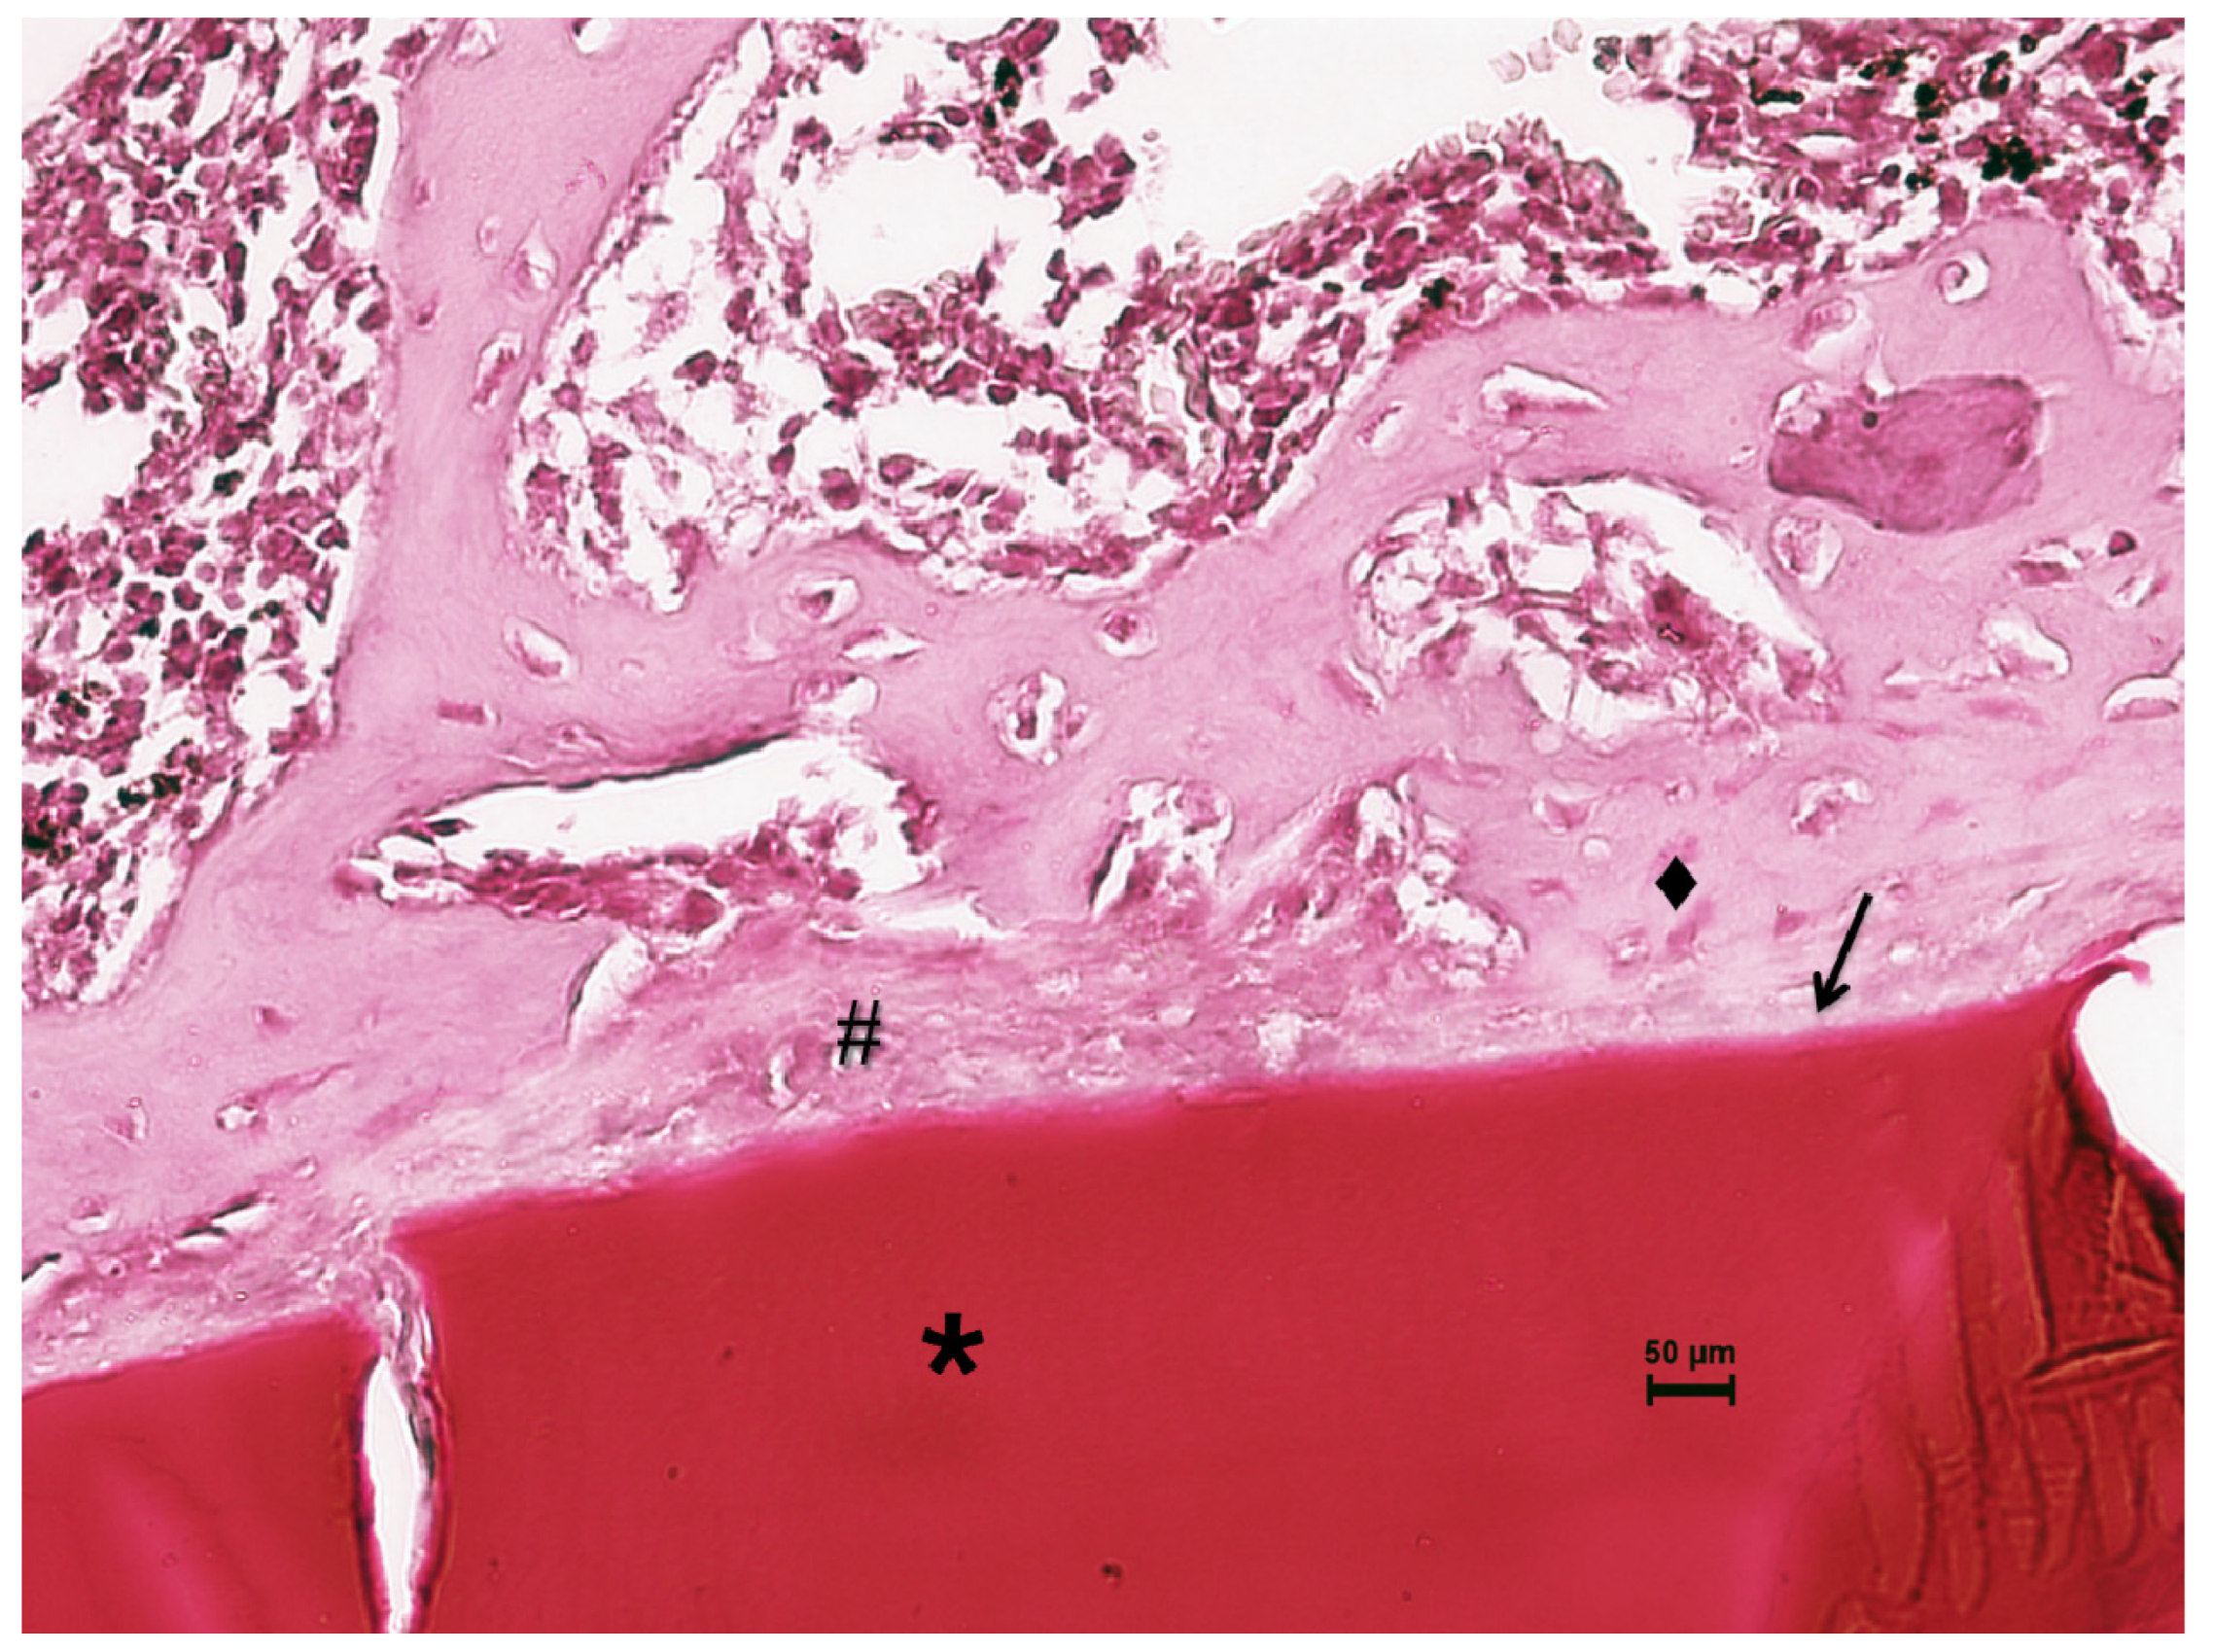

Figure 8.

Histological evaluation of CS at 14 days post-implantation. At the tissue–biomaterial interface there is reparative granulation tissue (#) and formation of woven bone tissue (♦), sometimes in close contact with the surface of the biomaterial (osseointegration ↑). Orig. Mag. ×400; H-E stain. * Pure chitosan (CS).

Fourteen days after the implantation of CS/Sol-Si and CS, there were no acute inflammatory infiltrates or multinucleated giant cells, indicating good biocompatibility of both materials. At the tissue–biomaterial interface, the clot was replaced by reparative granulation tissue with abundant fibroblasts and a new formation of woven bone tissue (immature bone, confirmed by polarized light microscopy), sometimes in close contact with the surfaces of both biomaterials (osseointegration) (Figure 8 and Figure 9). It is worth highlighting that histologically, larger areas of osseointegration were observed with CS/Sol-Si than with CS.